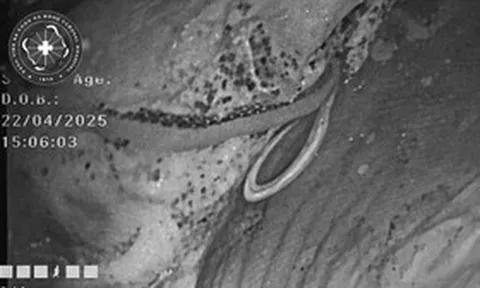

Nam thanh niên 26 tuổi phát hiện suy thận bởi dấu hiệu "vừa lạ vừa quen" ở mắt